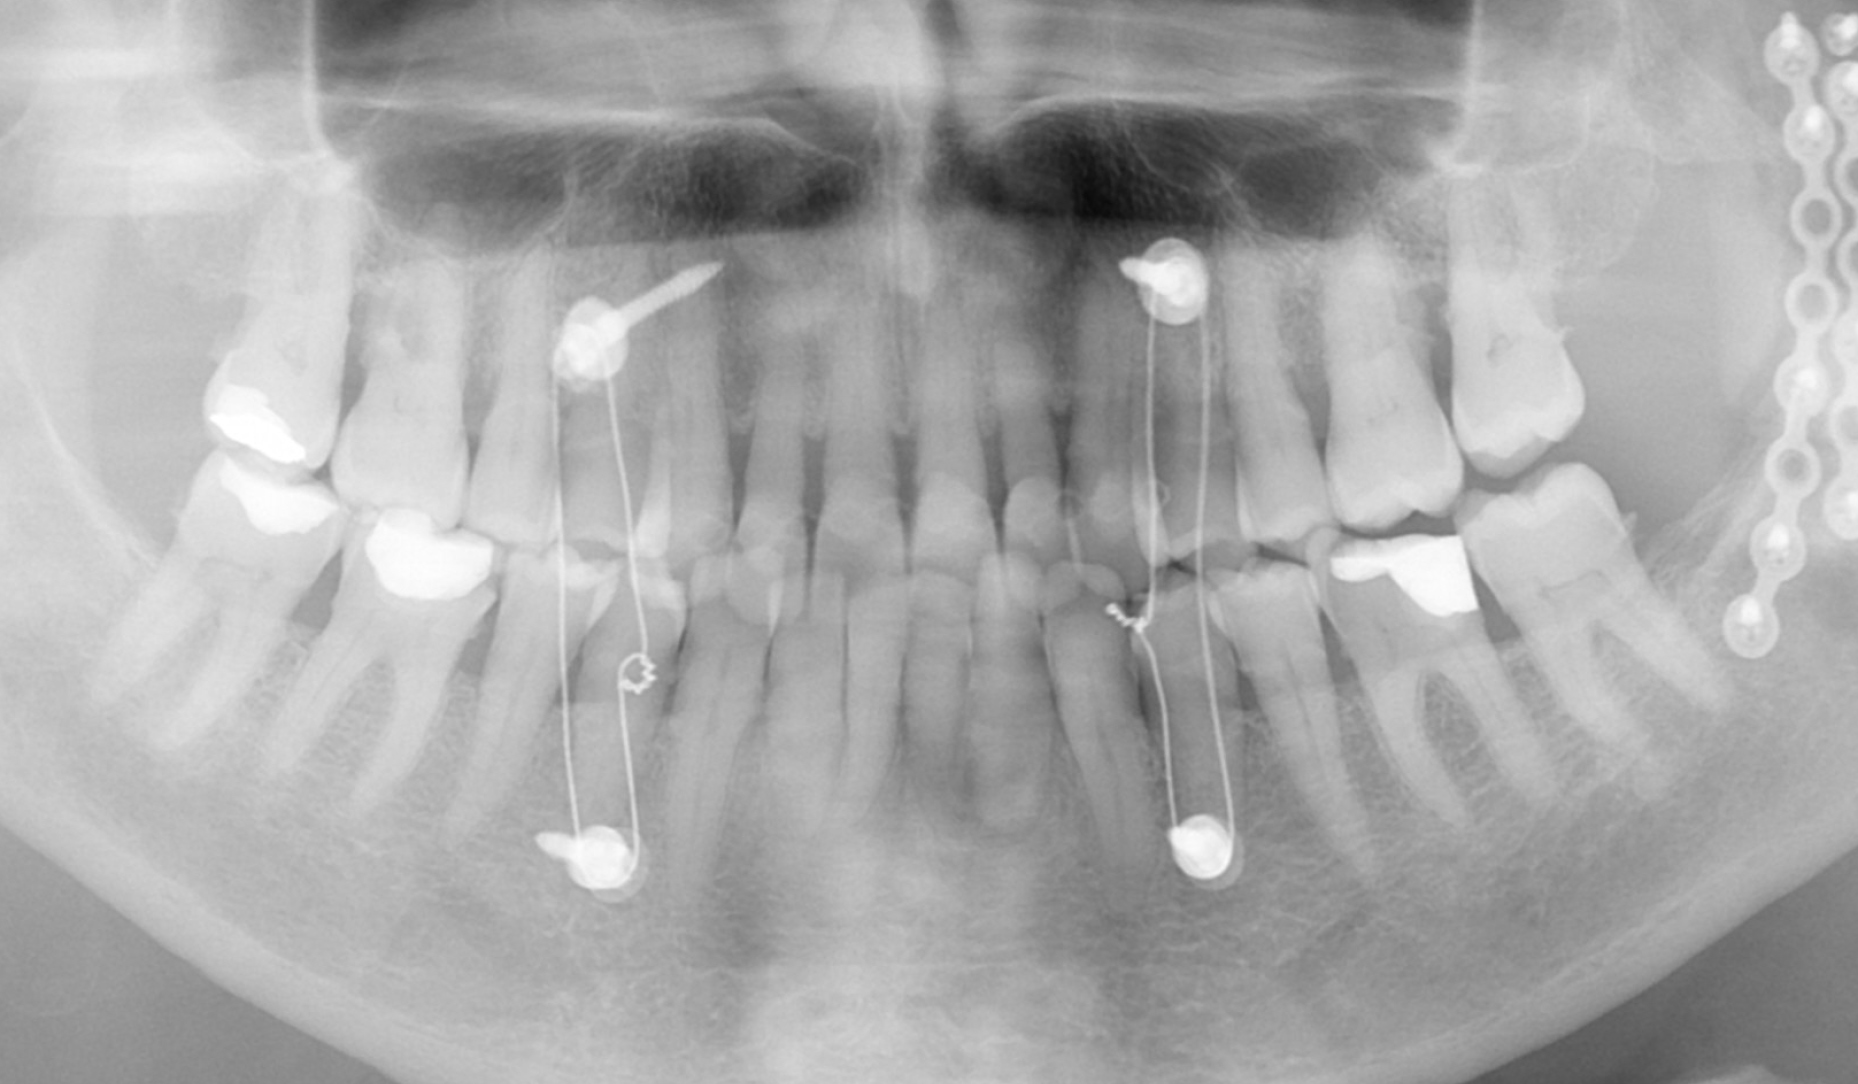

Do kliniki zgłosiła się 85-letnia pacjentka po osteosyntezie wieloodłamowego złamania żuchwy, którego doznała podczas upadku. W trakcie gojenia doszło do masywnej dyskluzji w lewym, tylnym obszarze żuchwy (zęby 34 do 37; notyfikacja FDI). Pacjentka chciała odzyskać prawidłową funkcję żucia w tym obszarze. Po leczeniu endodontycznym dwóch zwichniętych zębów siecznych centralnych, które zostały replantowane w szpitalu, oraz leczeniu periodontologicznym, zaplanowano podniesienie zgryzu po lewej stronie.

Ryc. 1. Stan przed leczeniem po złożonym złamaniu żuchwy – dyskluzja po lewej stronie.